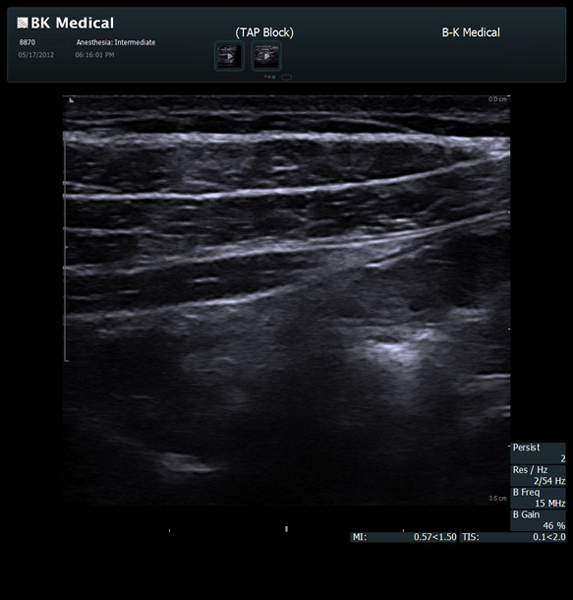

Enhanced Needle Visibility with Innovative X-Shine

X-Shine needle visualization option enhances the needle’s appearance in real time during in-plane procedures.

Transducers Designed for Guidance

BK Medical offers high-frequency linear transducers, imaging from 18-2 MHz for upper and lower extremities, and curved array abdominal transducer 8820e for special deep nerves or paravertebral/spinal applications. Our transducers provide superb detail that makes it easy to see your needle during procedures.